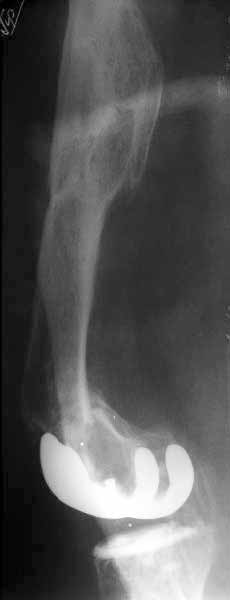

A male 41 years old transferred to our unit with 3 week old femoral fracture near the knee prosthesis after a mimimal fall. In 1994 he sustained multiple injury with open patella fracture (complicated with septic arthritis), and ipsilateral femoral shaft fracture treated by ex-fix.

TKA performed in 1998. In 2001 he got a periprosthetic fracture which was treated nonoperatively and healed with ~1 cm dorsal displacement of the distal femoral block. Knee ROM prior the recent injury was about 90-95 degrees. He didn't use walking aid.

Images attached.